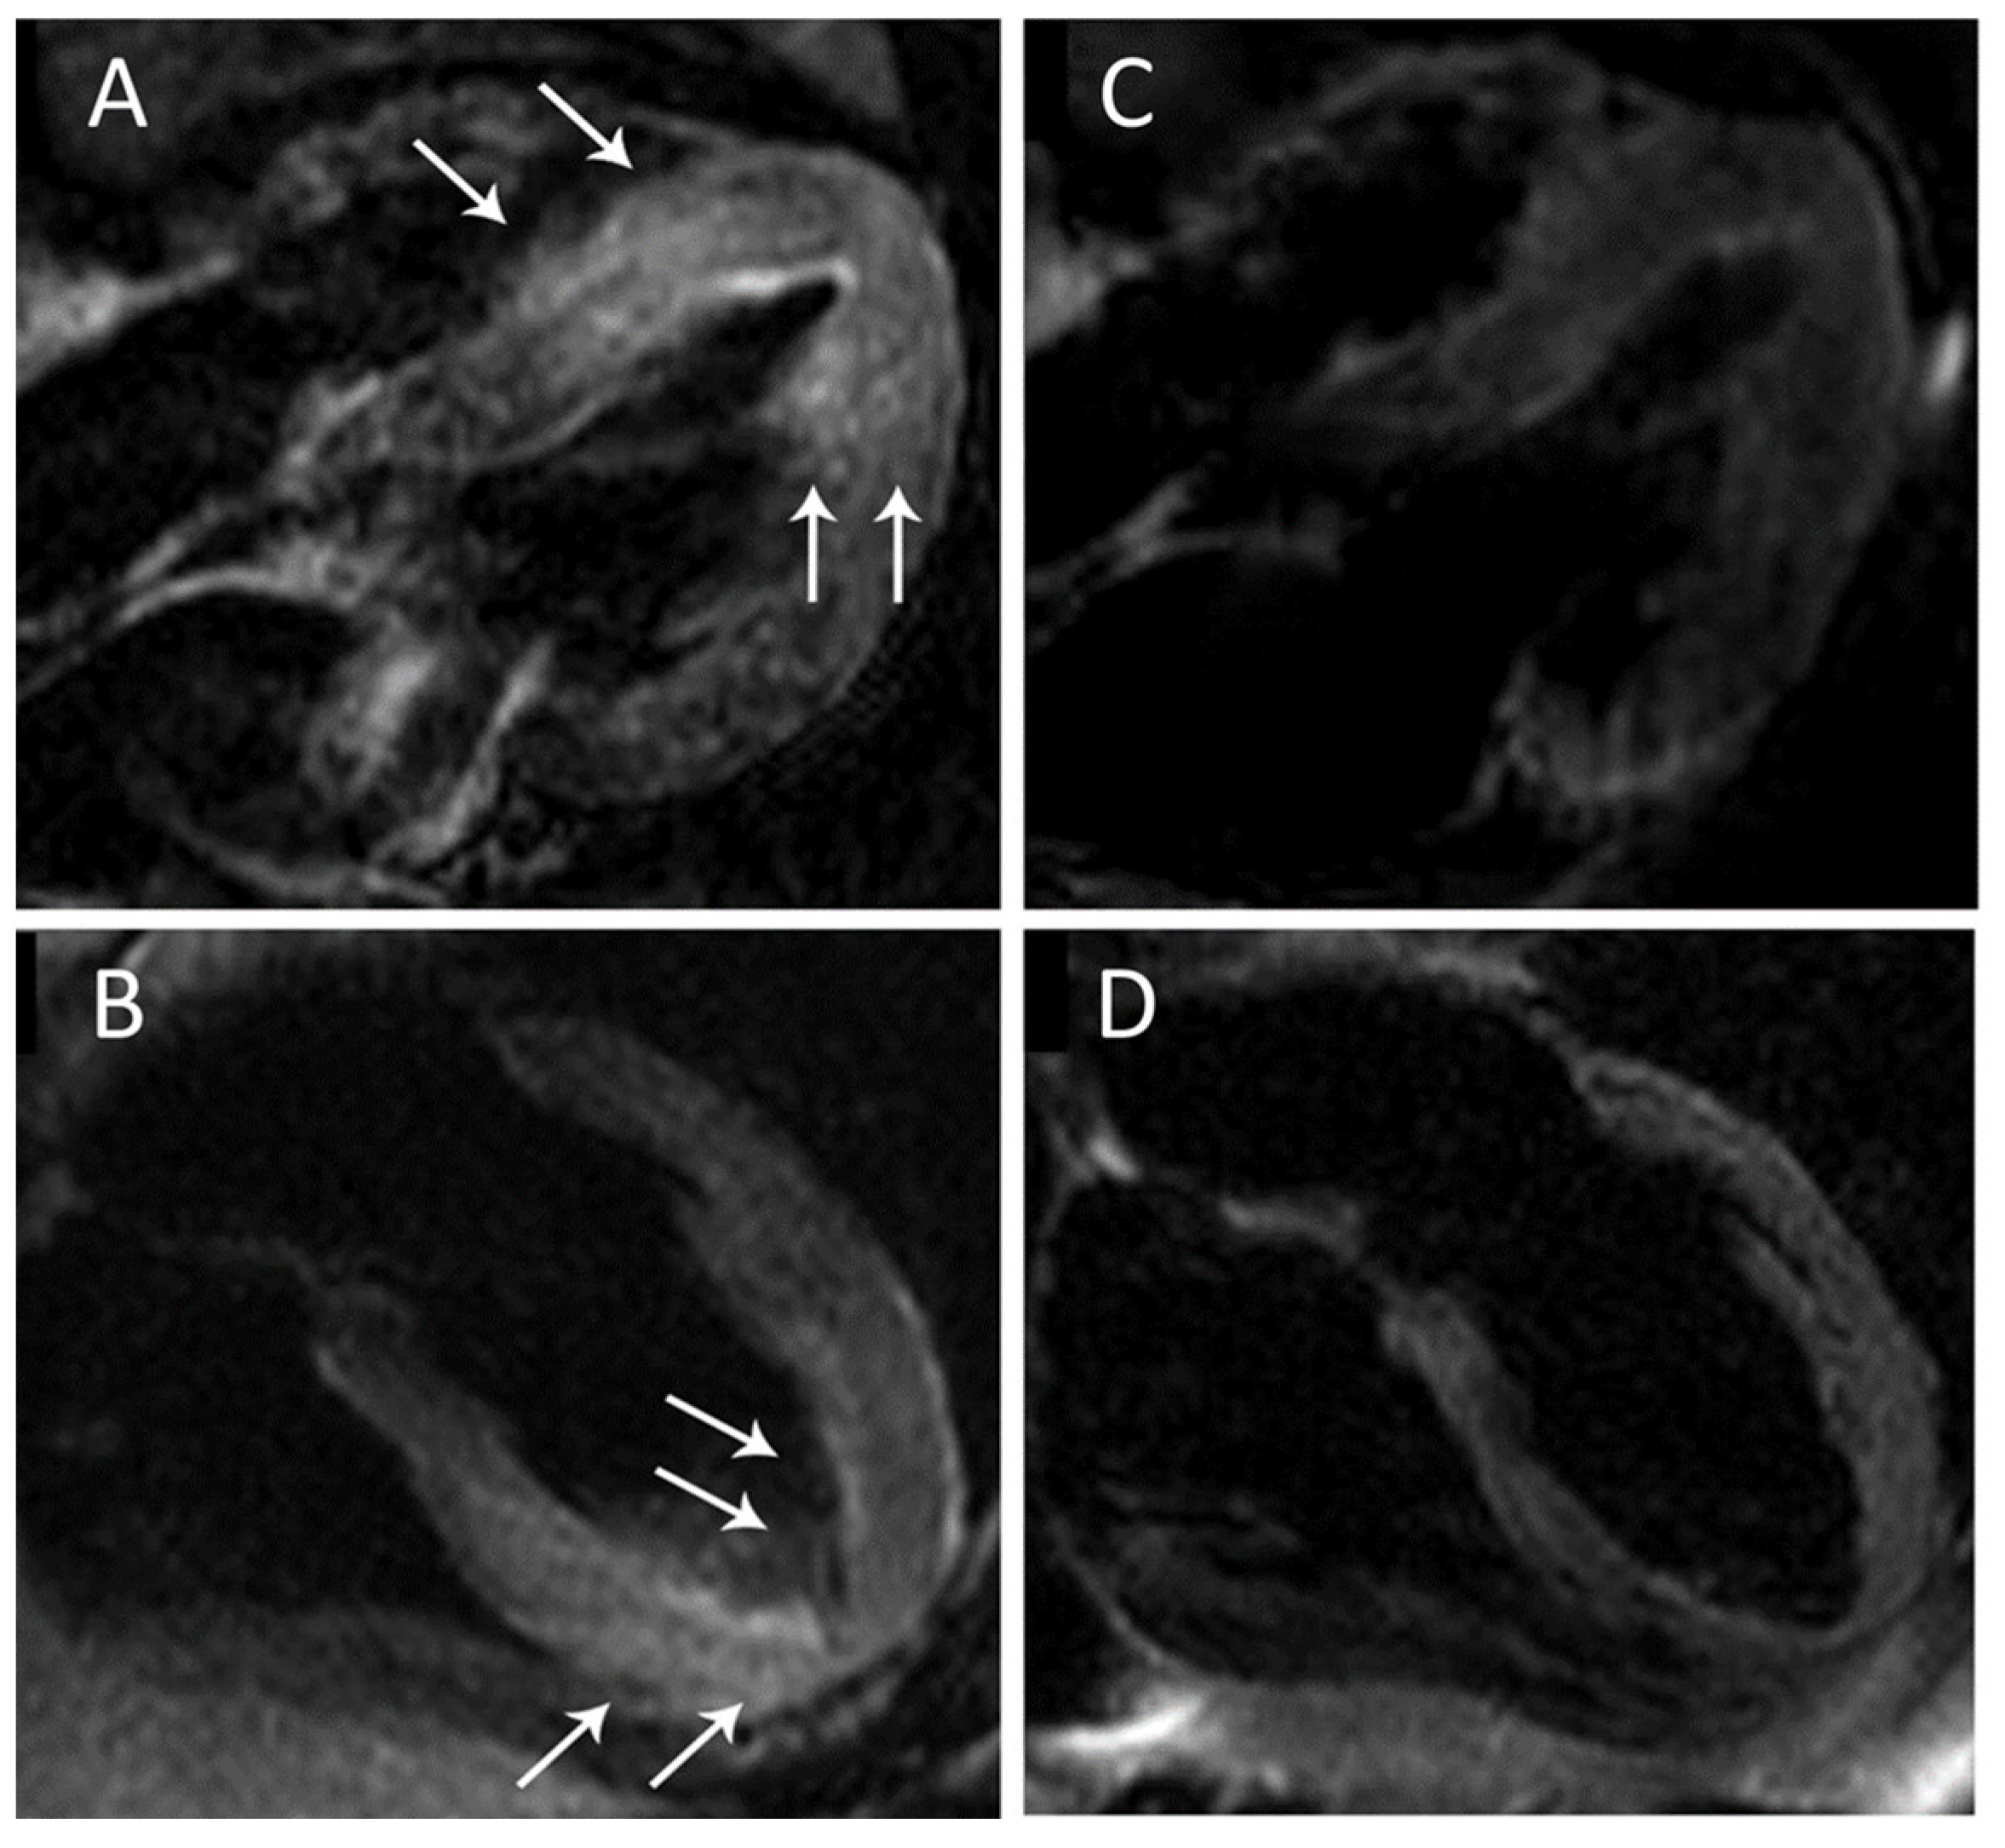

- Zorzi, A.; Mattesi, G.; Baldi, E.; Toniolo, M.; Guerra, F.; Cauti, F.M.; Cipriani, A.; De Lazzari, M.; Muser, D.; Stronati, G.; et al. Prognostic Role of Myocardial Edema as Evidenced by Early Cardiac Magnetic Resonance in Survivors of Out-of-Hospital Cardiac Arrest: A Multicenter Study. J. Am. Heart Assoc. 2021, 10, e021861. [Google Scholar] [CrossRef] [PubMed]

- Zorzi, A.; Susana, A.; De Lazzari, M.; Migliore, F.; Vescovo, G.; Scarpa, D.; Baritussio, A.; Tarantini, G.; Cacciavillani, L.; Giorgi, B.; et al. Diagnostic value and prognostic implications of early cardiac magnetic resonance in survivors of out-of-hospital cardiac arrest. Heart Rhythm 2018, 15, 1031–1041. [Google Scholar] [CrossRef]